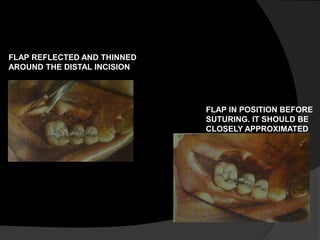

FLAP REFLECTED AND THINNED

AROUND THE DISTAL INCISION

FLAP IN POSITION BEFORE

SUTURING. IT SHOULD BE

CLOSELY APPROXIMATED